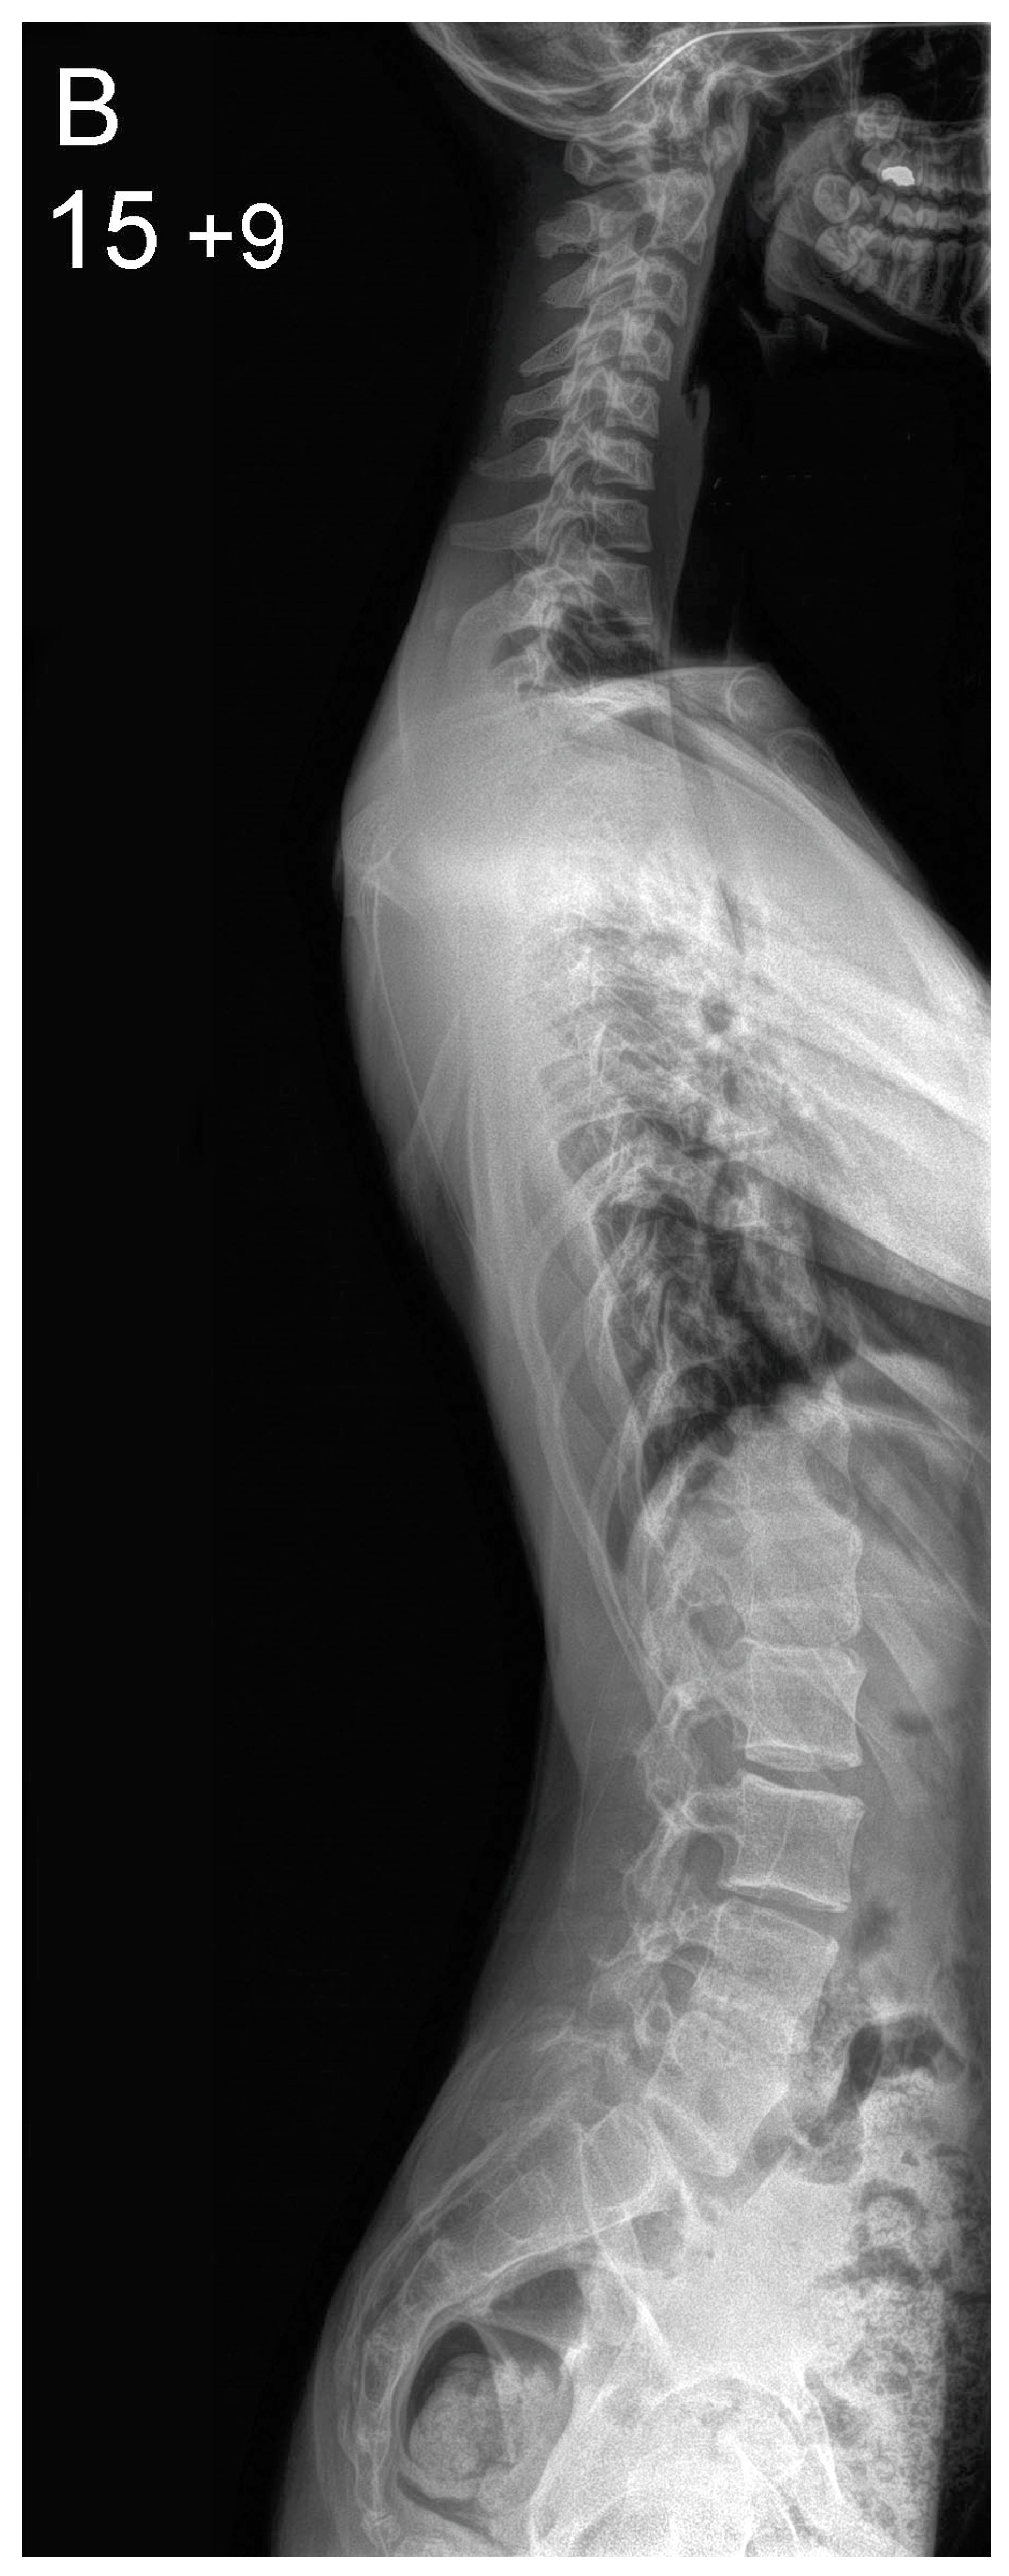

Figure 1.

Patient aged 15 years and 9 months with a right thoracic AIS producing thoracic translocation and listing of the trunk to the right, as well as thoracic flat back producing negative global sagittal balance of the spine and compensatory cervical kyphosis (A,B). The patient underwent posterior scoliosis correction using the AS technique which restored segmental and global coronal/sagittal spinal balance at latest follow-up (age 18 years and 8 months) into adult life (C,D). Clinical photographs demonstrate excellent correction of the coronal deformity and associated rib hump after scoliosis surgery (E–H).